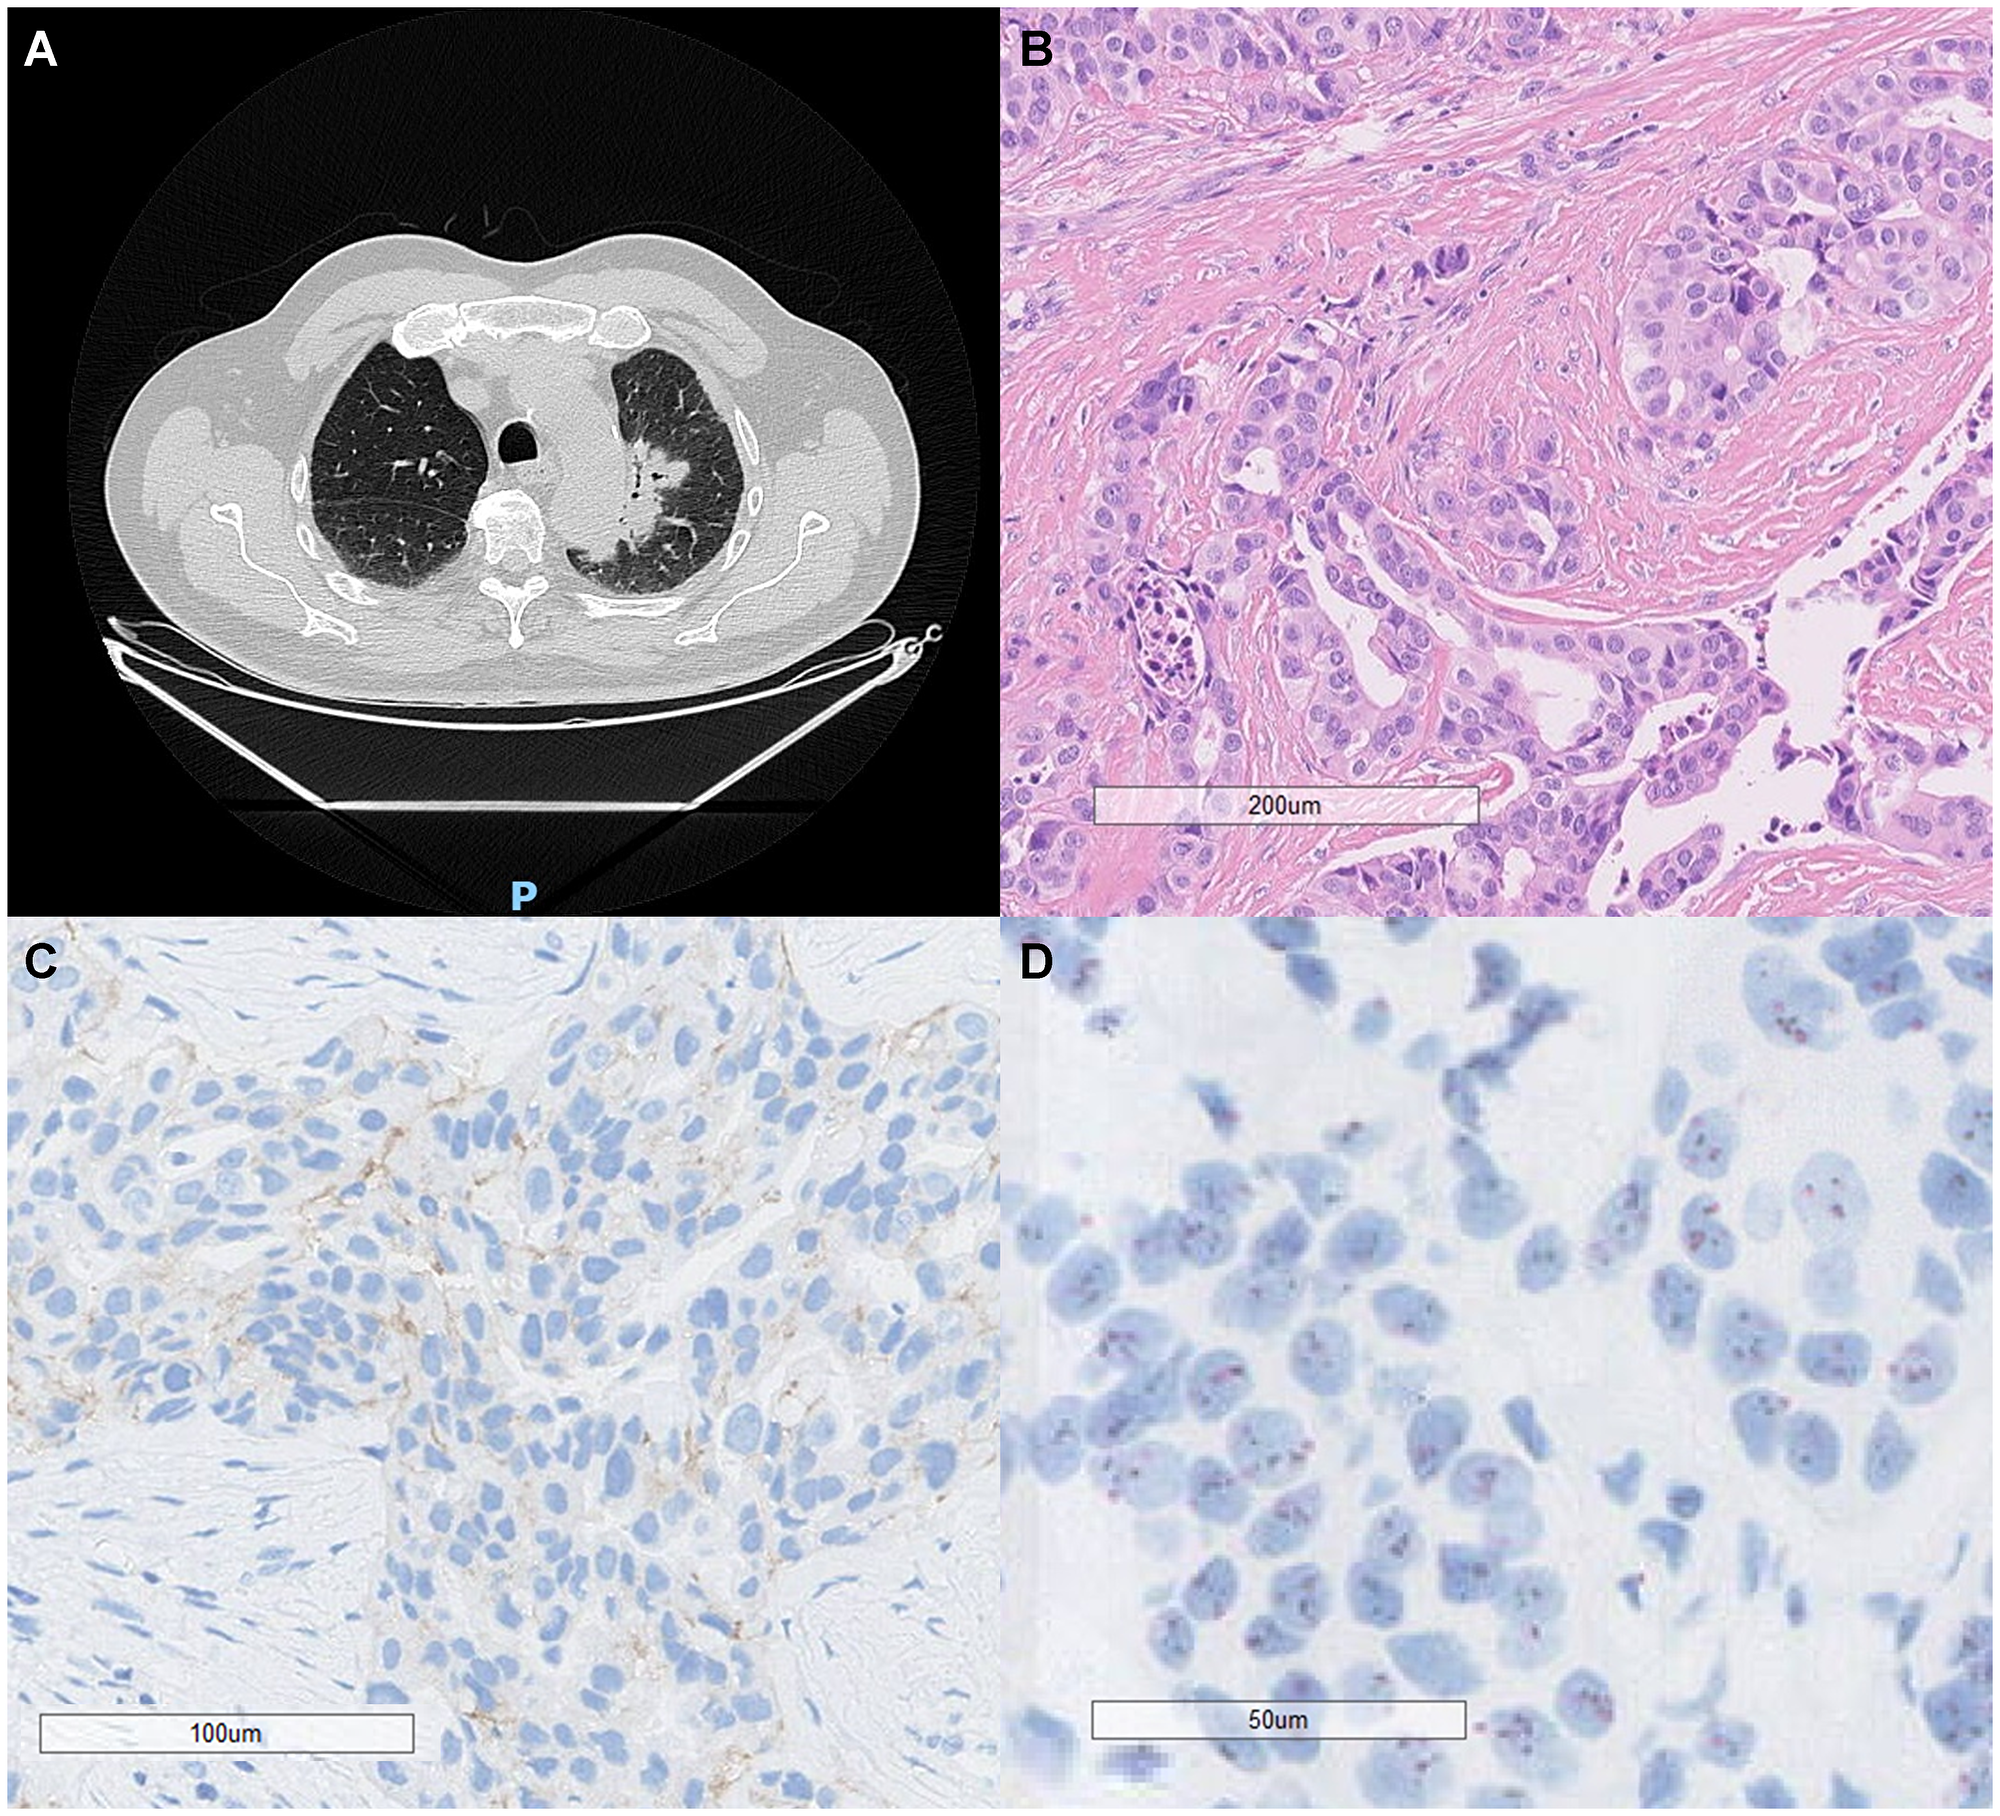

Radiological, histopathological, and molecular features of a HER2-amplified lung adenocarcinoma

Figure 3: Radiological, histopathological, and molecular features of a HER2-amplified lung adenocarcinoma.

(A) Chest computed tomography (CT) scan demonstrates a consolidative opacity with air bronchograms, surrounded by a faint ground-glass halo and lobulated margins, located in the visceral periphery of the apicoposterior segment of the left upper lobe. (B) Hematoxylin and eosin (H&E) staining reveals acinar-pattern adenocarcinoma with moderately differentiated tumor cells showing glandular architecture (scale bar = 200 μm). (C) Immunohistochemistry for HER2 (IHC) demonstrates a 2+ membranous staining pattern, focal basolateral and incomplete, moderate (scale bar = 100 μm). (D) Dual in situ hybridization (DISH) reveals HER2 gene amplification with an average of 4 HER2 gene copies per centromere (scale bar = 50 μm). These findings confirm the HER2-amplified status of the tumor and support its molecular characterization for targeted therapeutic strategies.